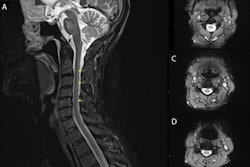

A: Coronal fluid attenuation inversion-recovery (FLAIR) MRI of the brain showing a large, well-defined, unilocular, cerebrospinal fluid-like cyst (*) located in the right parietal lobe. The cyst is causing minimal mass effect on the occipital horn of the right lateral ventricle (arrow) with mild surrounding vasogenic edema. Collapsed membranes are seen in the medial and inferior aspect of the cyst (open arrows). B: Axial T2-weighted MRI of the brain showing the right parietal hyperintense hydatid cyst (*). The cyst has a thin hypointense rim (arrow) with mild surrounding vasogenic edema along its anterior aspect. Collapsed membranes are seen in its medial aspect with a ball-of-wool pattern (open arrows). C: Axial T1-weighted MRI of the brain after gadolinium administration showing the right parietal hypointense hydatid cyst (*) with the nonenhancing collapsed membranes seen in its medial aspect. D: Single-voxel MR spectroscopy from the central cystic portion of the lesion showing increased choline, a small peak at 2.40-2.50 ppm representing pyruvate and succinate (oblique arrow), and a large abnormal peak at 2.2 ppm representing glutamate/amino acids (horizontal arrow). Pyruvate and succinate are well-known metabolic end products arising from microorganisms. E: Single-voxel MR spectroscopy from the peripheral solid portion of the cystic lesion showing increased choline/N-acetyl aspartate ratio. All images courtesy of BMJ Case Reports.In this case, MR spectroscopy of the central cystic part of the lesion demonstrated elevated choline, as well as pyruvate and succinate picks, while also showed an increased choline/N-acetyl-aspartate (NAA) ratio and a large peak of lipids, according to the authors.